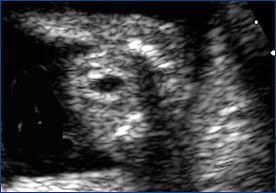

After successful treatment, the donor bladder begins to fill (small black circle in the middle of the abdomen) and the blood flow in the umbilical cord improves (right image).